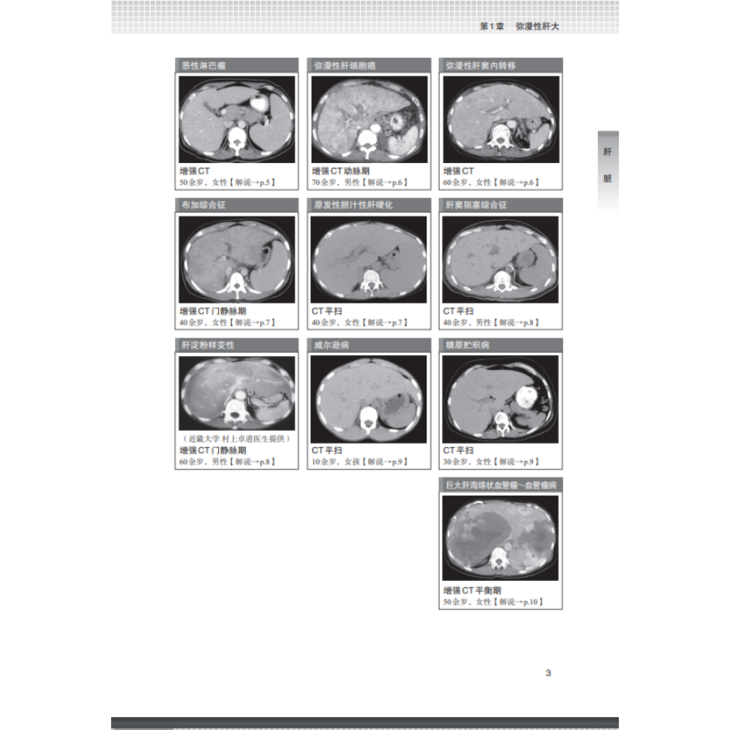

第1章 弥漫性肝大 2

表现为弥漫性肝大的疾病 4